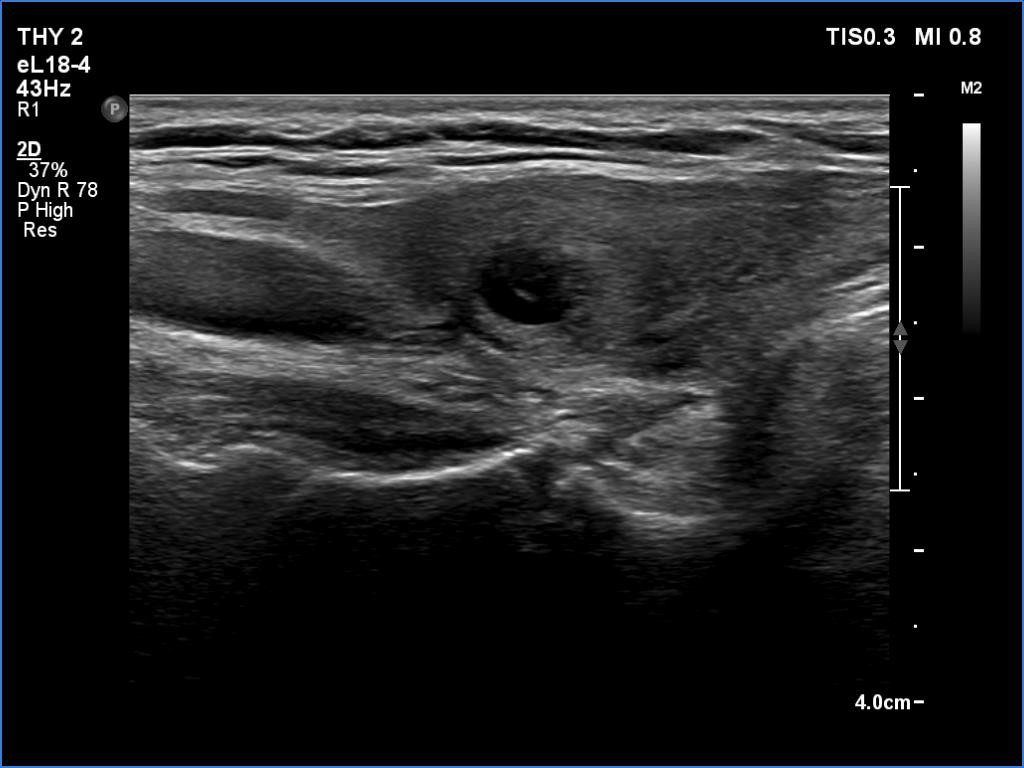

Subacute granulomatous thyroiditis - case 1514 (ultrasonographic picture 4)

Right lobe, another longitudinal scan. The echo amplifying dorsal to the lesion stands for being the lesion cystic.